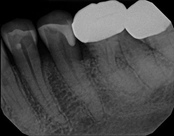

Missed canals and sclerotic orifices/canals:

Before

4-month post-opIn this situation, some would say the canals are so “calcified” that root canal treatment can’t be done; or sometimes the canal can’t be found. And because of that the tooth would need an extraction and an implant. In some instances, root canal therapy can’t be done but that does not mean the tooth is a loss. The solution is micro-apical surgery, an apicoectomy.